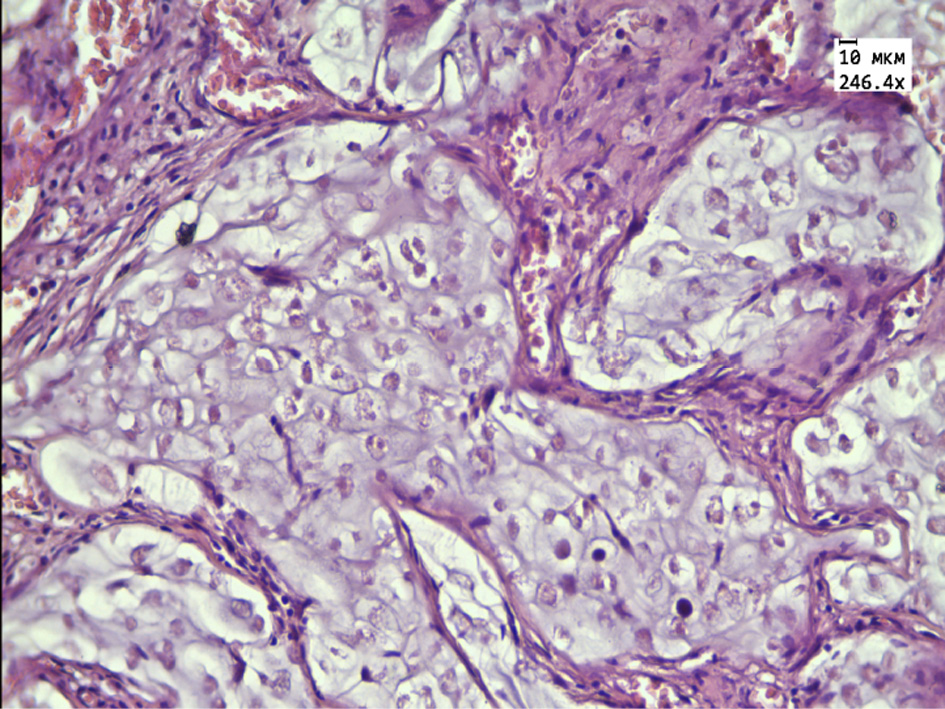

In the group of rats receiving aqueous extract of thyme, the tumor is represented by small rounded cells with a reduced flattened nucleus located on the periphery of the tumor tissue. The central parts are represented by extensive necrotic foci, a large number of “shadow cells” and thickened connective tissue partitions with a large number of blood vessels, as well as extensive clusters of tumor cells with signs of karyopycnosis, nuclear chromatin condensation and karyorexis, and a large number of apoptotic cells (Fig. 3, 4).

Figure 3 – Histological structure of transplanted hepatic cancer in the group receiving aqueous extract of Thymus marschallianus Willd.

Note: necrotic foci of tumor tissue (black arrow), thickening of connective tissue partitions (white arrow). Stained with hematoxylin and eosin. Magnification 246.4×.